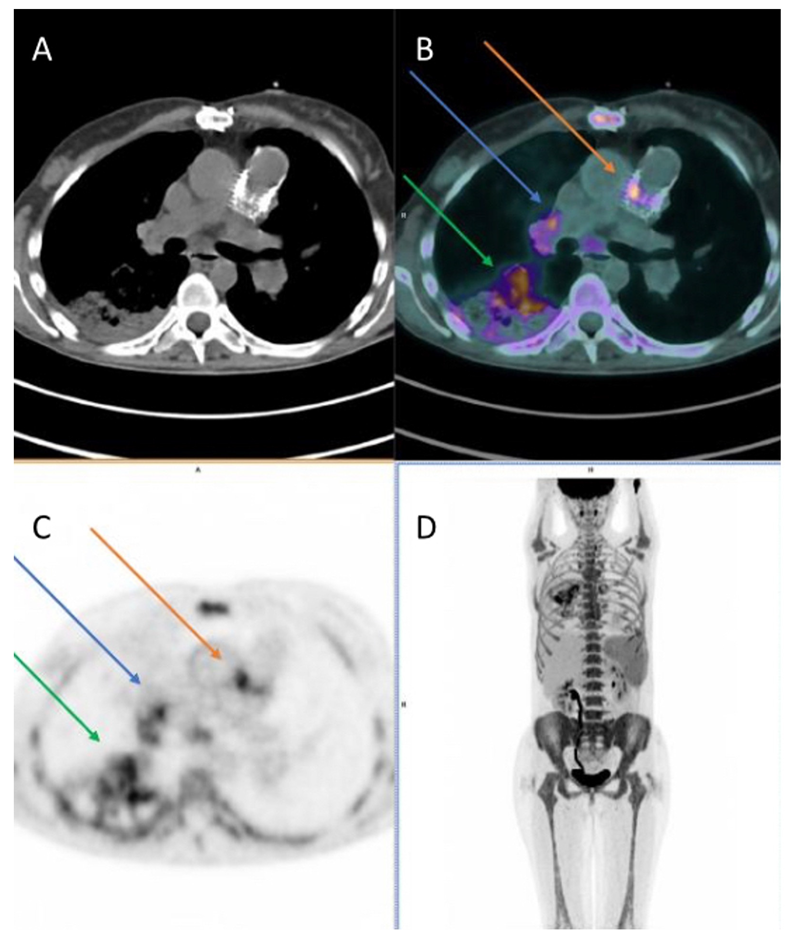

Figure 3. Cardiac computed tomography infective endocarditis visualisation. The images show right-ventricular pulmonary artery (RV-PA) conduit involvement (panels (A,B)) and systemic to pulmonary shunt involvement with a calcified lesion (panel (C,D)). The arrows indicate the vegetations.

In this context, Nagiub M. and colleagues presented their single-centre retrospective experience of pediatric patients with CHD and diagnosis of IE in which they described a high proportion of right-ventricular pulmonary artery (RV-PA) conduit involvement (Figure 3) as well as IE of the aortic valve. CCT also demonstrated thromboembolism, pseudoaneurysms, prosthetic valve perforations, and prosthetic valve leaks [6,54]. Furthermore, they discussed more peripheral, multi-site imaging to assess for vegetations and emboli (present in around 20–50% of the cases) [20].

In our own centre’s experience (AOU “Ospedali Riuniti’’, Ancona, Italy), the presence of a ventricular septal defect with their associated vegetations along with systemic to pulmonary shunt localisation present particular challenges (Figure 3). In addition, a recent meta-analysis has shown CCT demonstrated good diagnostic accuracy in terms of assessing valvular and periannular complications of IE. Of note, TOE remained superior for detecting valve leaflet defects [6].